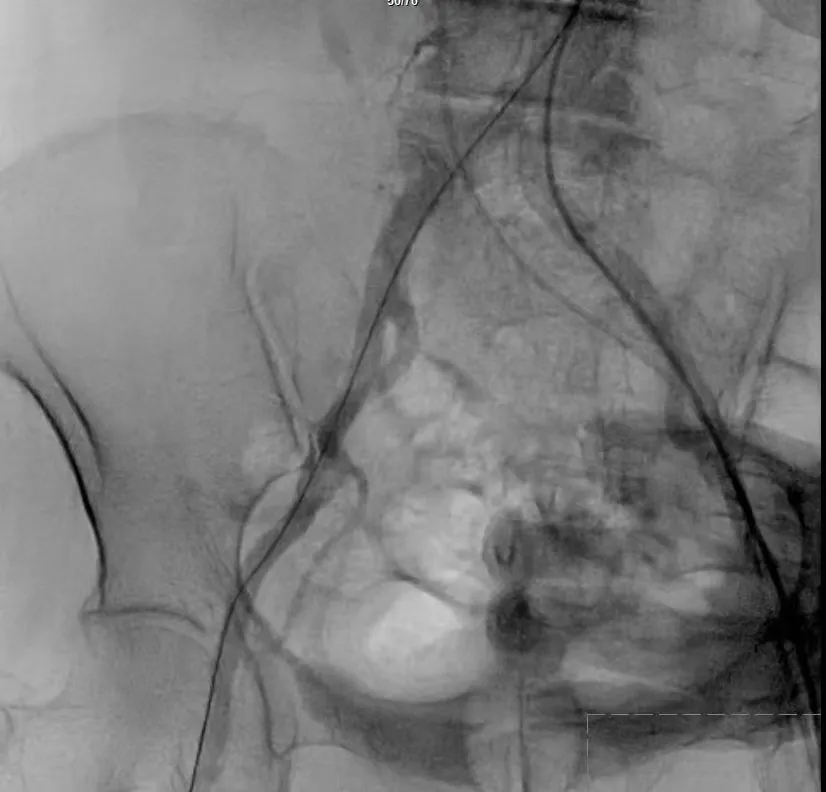

手术过程严谨有序:经术前精准评估与周密准备,团队成功送入预先装载的自膨式支架瓣膜输送系统,顺利完成过弓、跨瓣操作;经造影定位后,在180bpm快速起搏下精准释放瓣膜。瓣膜释放后,术中实时超声显示根部瓣架形态良好、启闭正常,瓣叶中心及瓣周未见反流;造影显示瓣膜位置满意、形态良好,冠脉显影清晰,入路血管无损伤,历经90分钟后,手术圆满成功。

术中影像